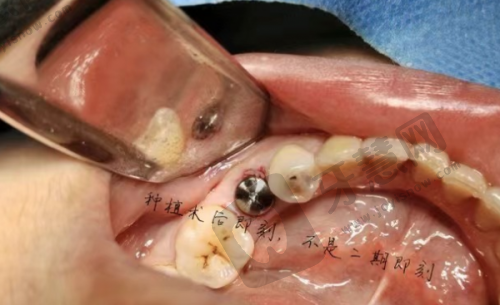

李刚医生:作为“立得用”种植体系的实践者,在即刻种植与即刻修复领域有独到见解。主攻半口/全口牙缺失的即刻功能重建,通过术前数字化模拟设计,拔牙后同步完成种植体植入,术后肿胀轻微,受上班族患者青睐。

刘成医生:从事口腔临床工作10余年,完成种植病例近万颗。擅长“立得用”种植牙体系、即刻种植、即刻负重等新技术,对疑难种植病例经验多。对待患者如亲人,耐心解答疑问,术后还关心患者修复情况。